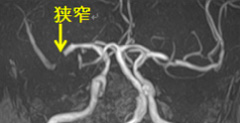

頭部MRA

頭部MRA

手術前

手術前 手術後